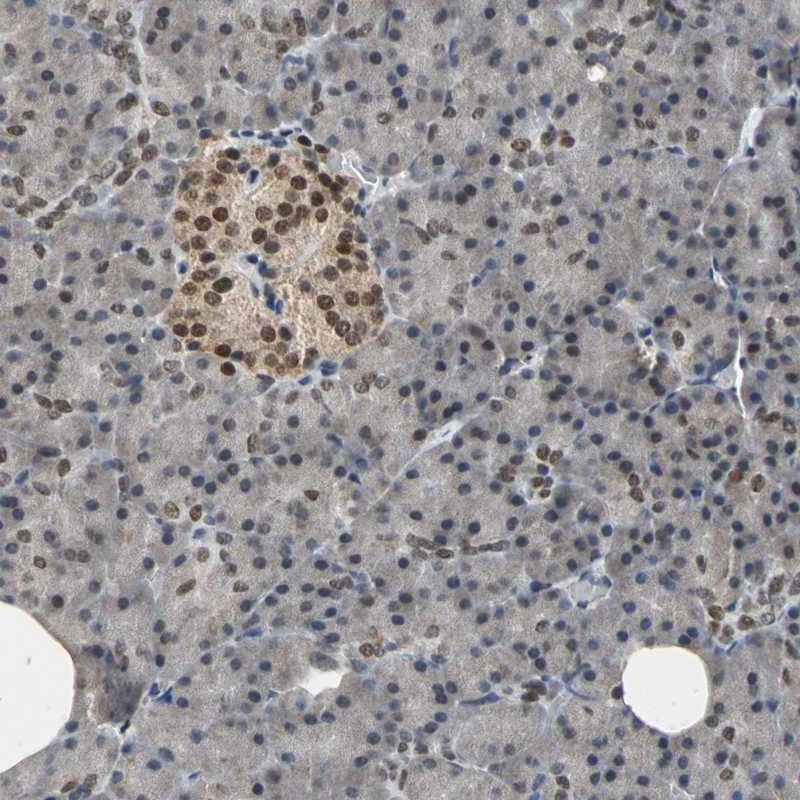

Immunohistochemical staining of human pancreas shows strong nuclear positivity in islet cells.